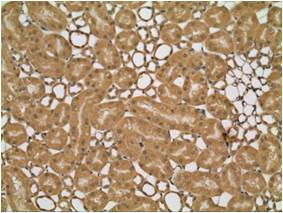

Wide use of high speed CMOS camera

High sensitive observation of 3 mega pixel